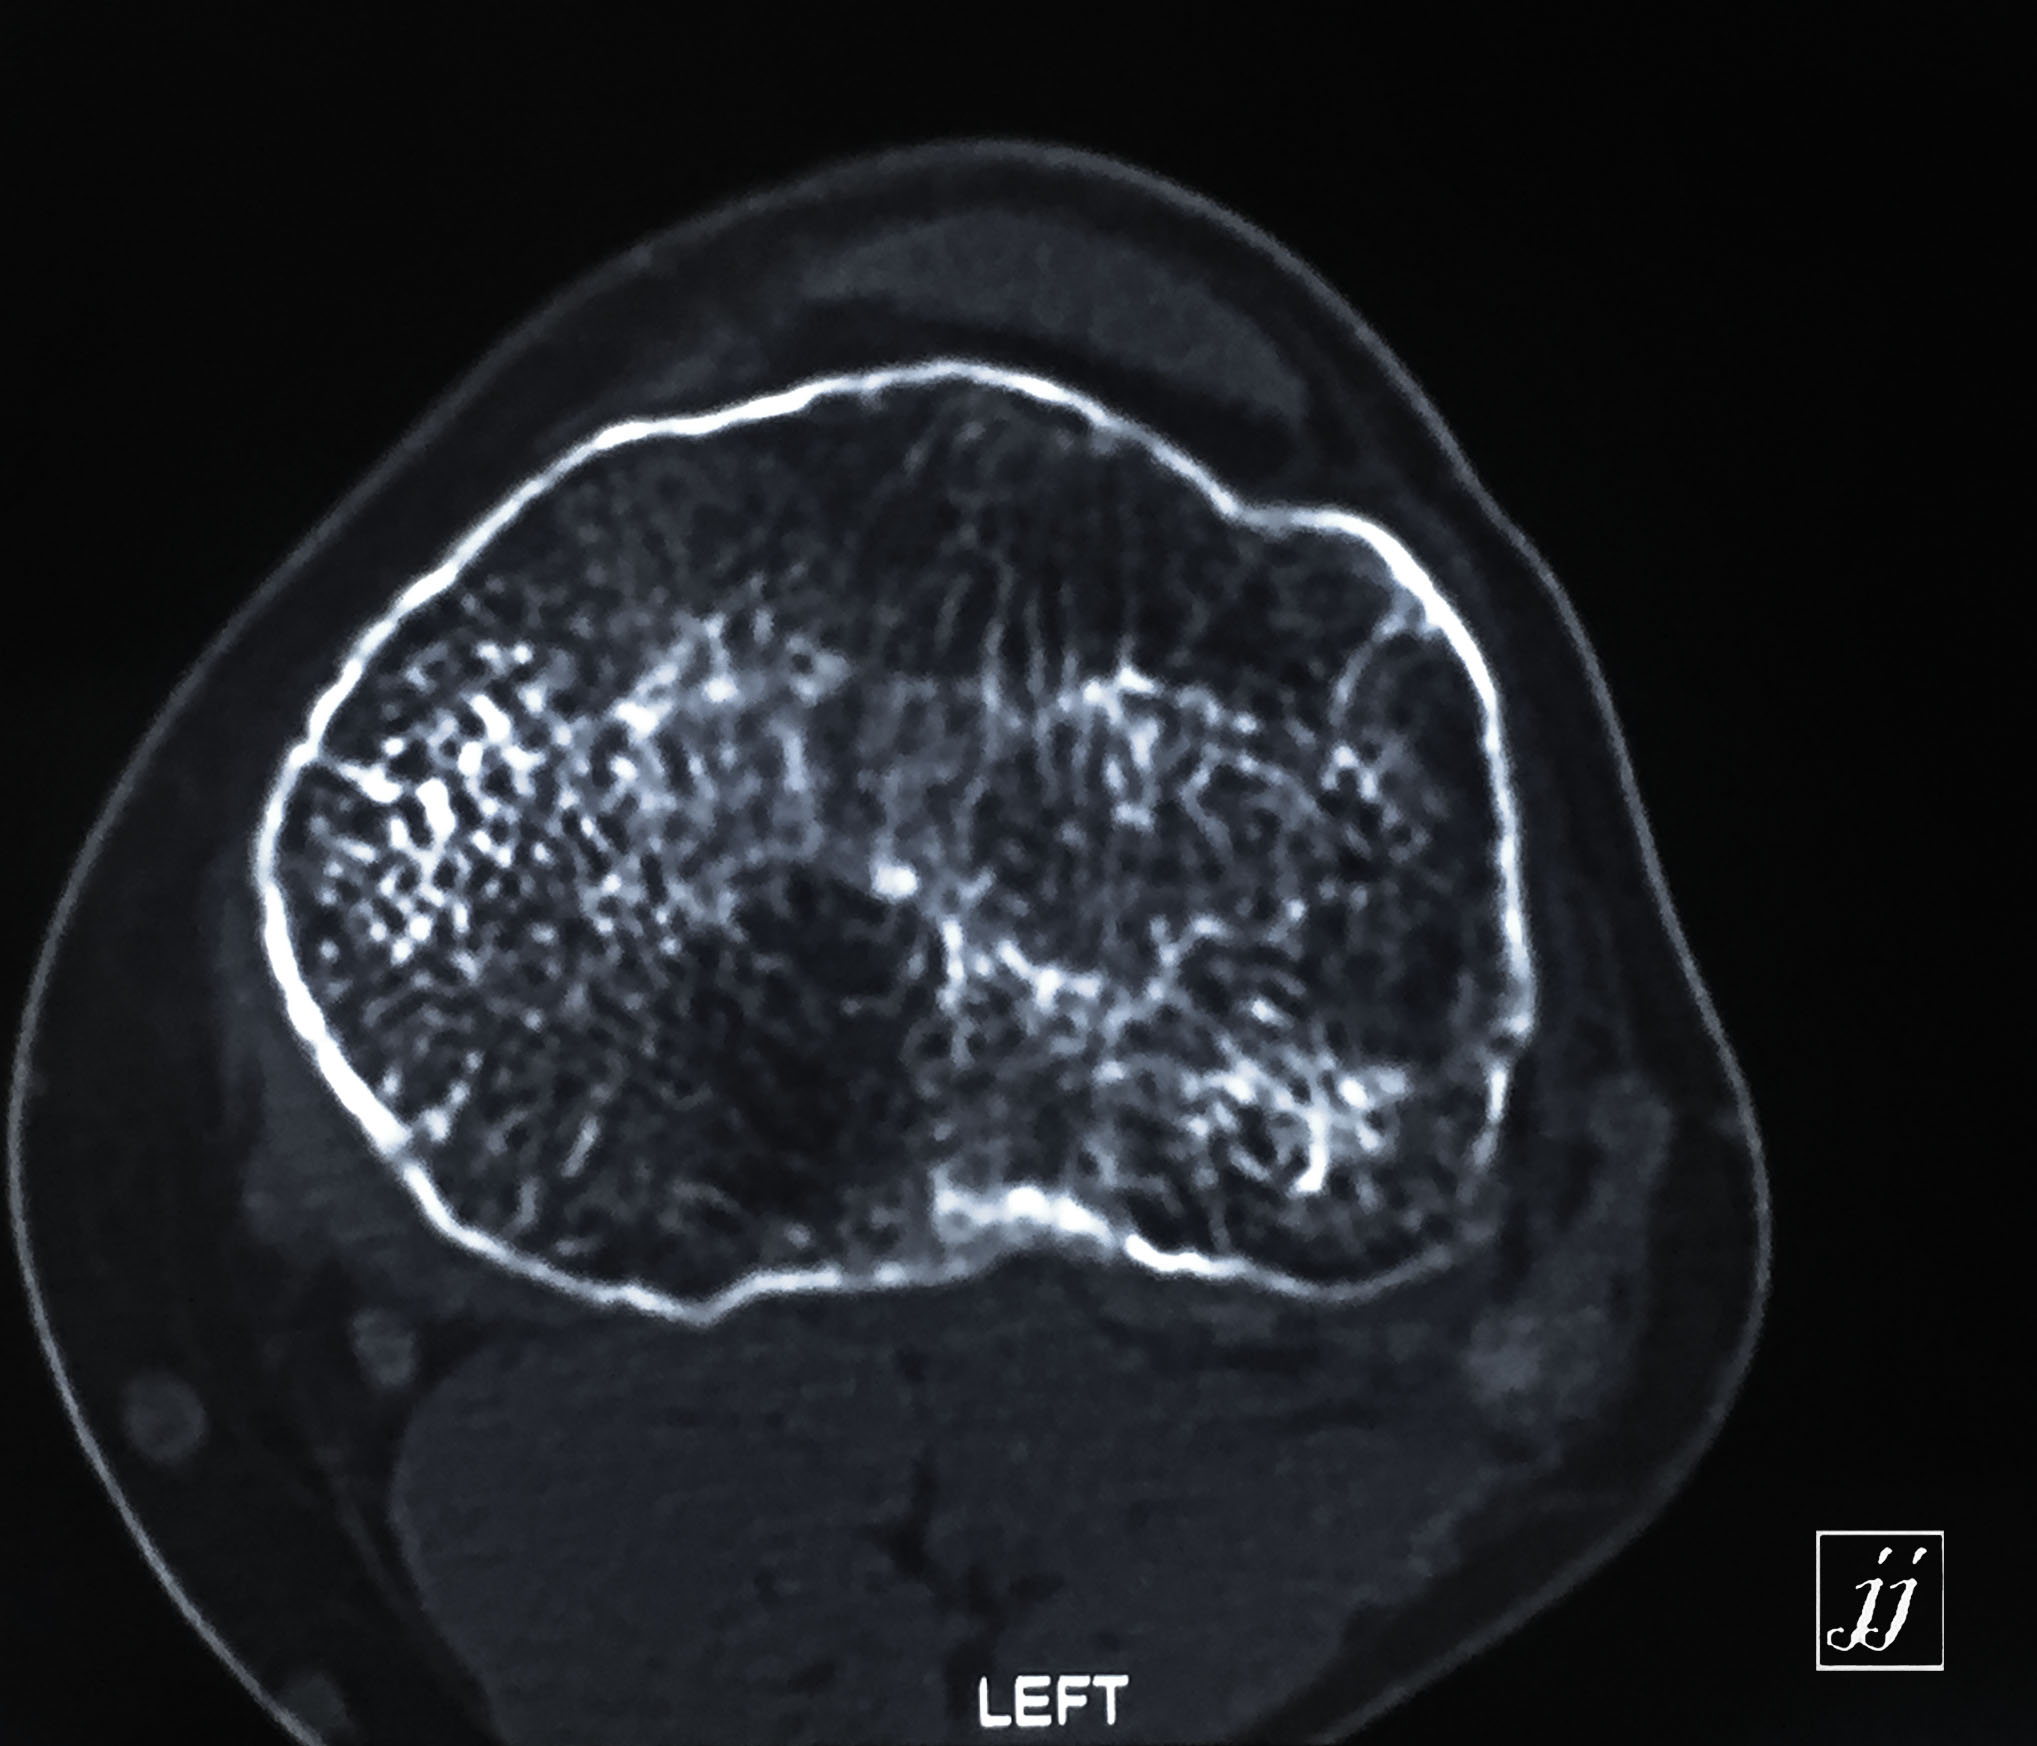

MSK- proximal tibia fracture and infection (25)